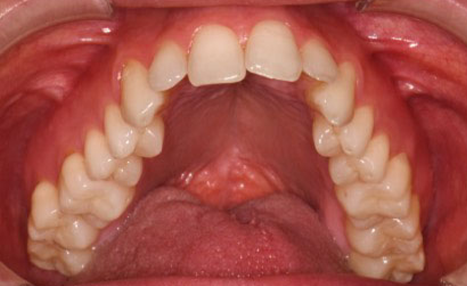

The final 4 months were focused on arch coordination and detailling.

Individually coordinated stainless steel archwires, using the WALA ridge described by Dr. Andrews as the reference

(image: Finishing wires)